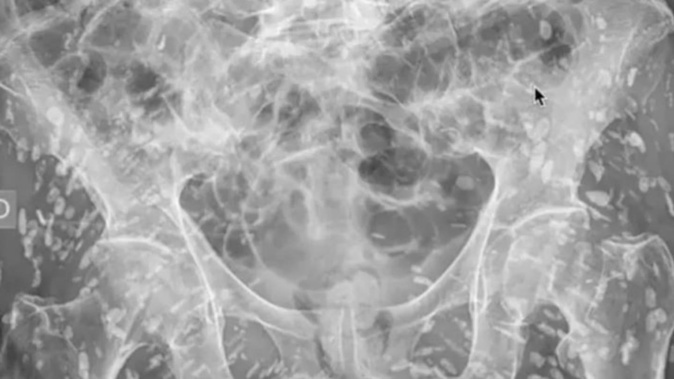

'Most insane X-ray I've ever seen': Doctor horrified after sick discovery

A doctor was left stunned after an X-ray revealed a man infested with hundreds of tapeworm eggs.

United States doctor Dam Ghali shared the image of an unnamed patient, claiming it was “one of the most insane X-rays I’ve ever seen”.

When taking an X-ray of the pelvis for a patient, he quickly discovered the man was infested with hundreds of tapeworm eggs.

“What is jumping right out off the screen at us is this femur is riddled with these linear densities and they’re everywhere. You can’t even begin to count them all. So what the hell are they?” he explained while examining the X-ray.

“This is a condition known as cysticercosis. Essentially these are larval cysts of taenia solium – also known as the pork tapeworm.”

He said in this case the cysts have moved to the muscular and soft tissue regions of the hips and legs in their hundreds.